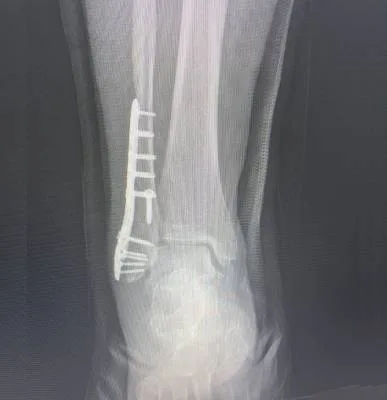

I had surgery with Dr. Haytham, and I’m very happy with the results. He previously operated on my leg after a fracture, and that surgery was very successful. Recently, I had another surgery on my knee, which was done in the simplest and most professional way. After the operation, I was able to return to my normal life — I can play football and be active again after a long time of not being able to. Dr. Haytham and his team took great care of me throughout the process, and I truly thank him for his excellent work and dedication